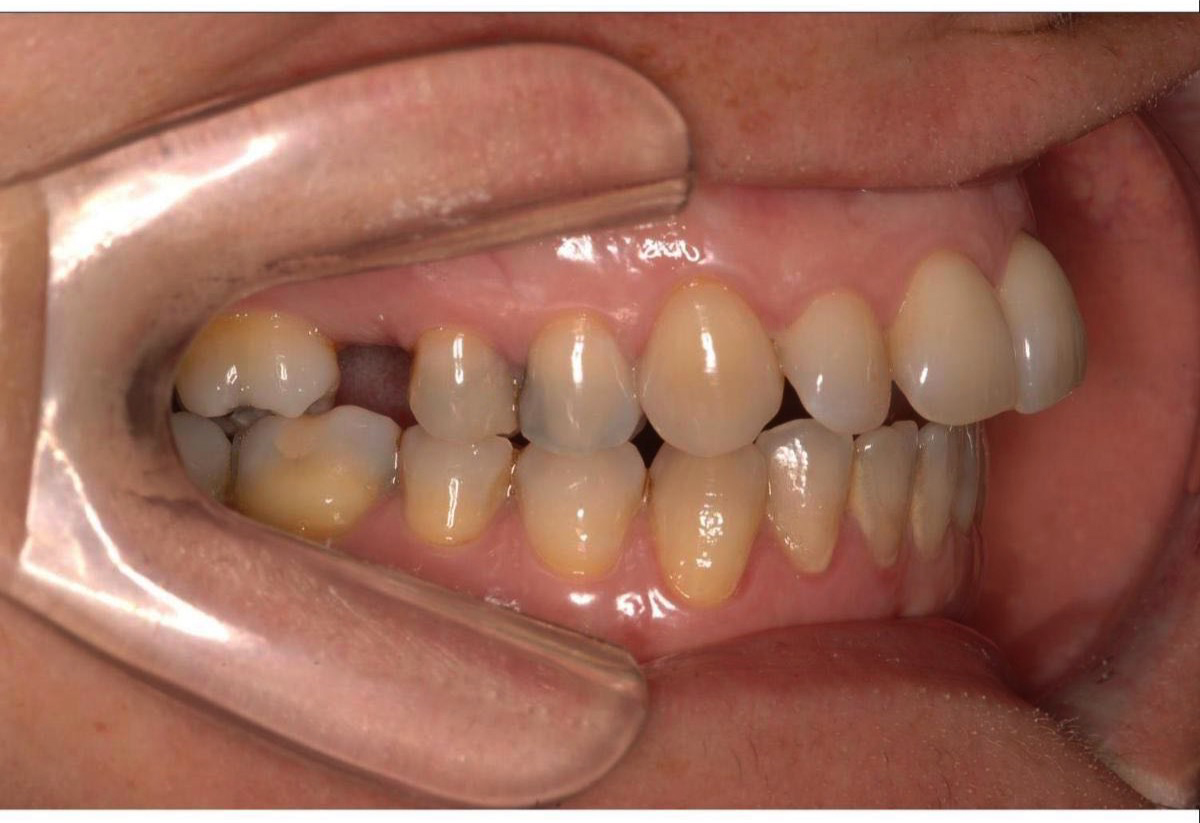

Mordida cruzada lateral

Se produce cuando los dientes de la arcada superior muerden por dentro de los inferiores en el segmento lateral y pone de relieve una falta de coordinación en anchura entre el maxilar superior con sus dientes y el maxilar inferior con sus dientes.

La mordida cruzada puede aparecer en un lado o en los dos, puede afectar a todos los dientes o sólo a uno, es decir existen múltiples formas de presentación (según una clasificación reciente hasta 21 posibilidades) y cada una requiere de abordaje diferente.